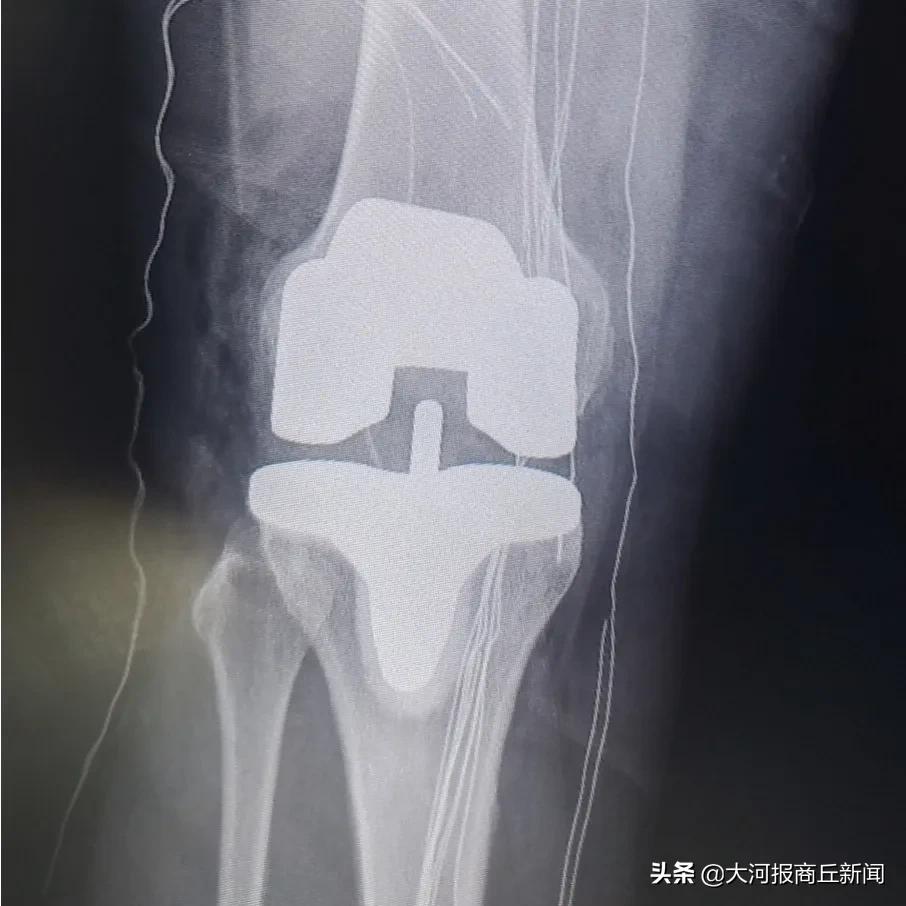

3月2日下午,豫东名医、骨科专家殷晓东院长领衔的柘城县中医院骨科团队在短短三个小时内完成四台人工膝、髋关节置换,其中包含一例高难度高龄患者双髋关节置换,非常时期下骨科团队丰富的经验和精准的操作技术再显不凡身手,较平均用时节约了一半时间,是柘城中医院开展关节置换技术多年来再次跑出的中医院新速度。

▲术后第二天,患者自行下床锻炼,全程无痛感

近年来,柘城中医院骨科一直致力于引进国内外各项先进技术,用于治疗骨关节疾病。在治疗股骨头坏死、膝关节骨性关节炎以及腰间盘突出症等疾病方面形成了独特的三阶梯式治疗方法。术后第二天即可下床走路,快速康复重建关节功能,截止目前,已成功完成了多例多关节同时置换及数十例百岁老人置换病例,受到了患者们的广泛赞誉。